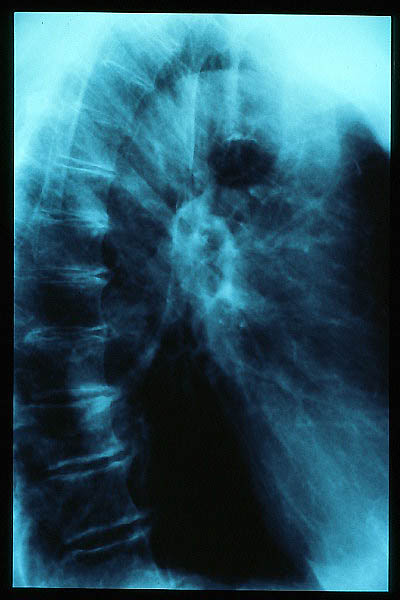

TBC pulmonar antigua